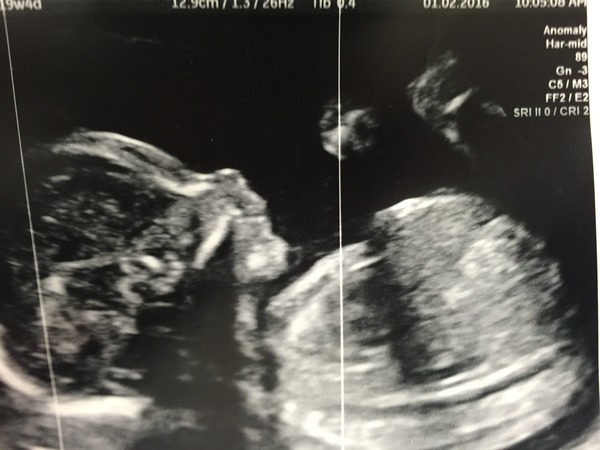

Hi all just received the all clear at our 20week scan, so relieved!!! Picture to follow. Thank you for all the good wishes, it really helped this morning. I got no sleep at all last night!

Eastend2015 · 01/02/2016 11:15

Pic attached!

Eastend lovely pic, I think I'd be really impatient to meet my LO after seeing that Smile. It's another scan for me in 10 days, if the sac has grown to over 25mm, not grown anymore or reduced, it'll be diagnosed as a MC. Otherwise it's wait and see Hmm.

east lovely picture Hun. Absolutely perfect I bet your beaming. Half way there :). Did you find out if you were having a baby blue or baby pink?